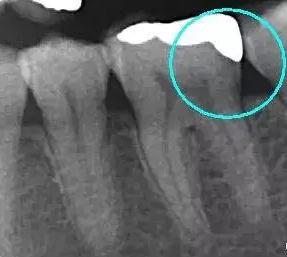

从下面这张X线中可以看出,嵌体远中边缘没有悬突,与牙体边缘密合相接。